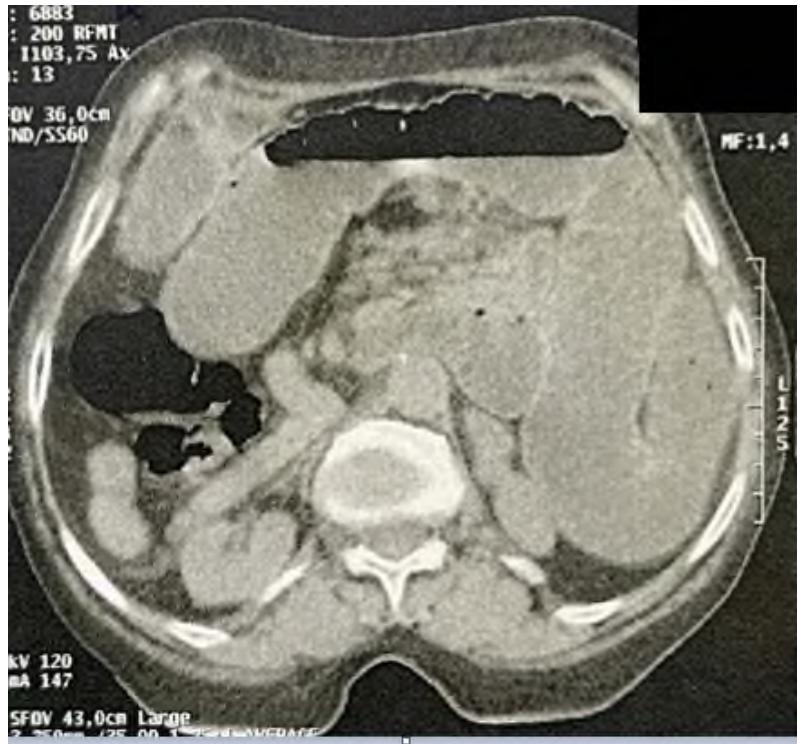

Situs inversus totalis is a rare congenital malformation that results in mirror positioning of the thoracic and abdominal organs. Situs inversus abdominalis is a right-left inversion limited to the abdomen; The association of situs inversus with intestinal band occlusion is infrequent; We report a case of acute intestinal obstruction associated with situs inversus abdominalis, the diagnosis was confirmed by abdominopelvic CT scan, and the treatment consisted of a gallbladder resection with anastomosis, with good postoperative results.

Intrusive intestinal obstruction diagnosis in abdomen.